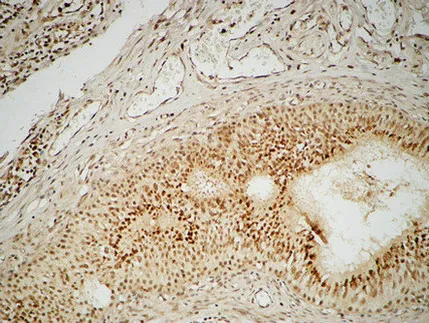

FEN-1 Rabbit Polyclonal Antibody

Cat: APRab10901

Size1:50μl Price1:$118

Size2:100μl Price2:$220

Size3:500μl Price3:$980

Size2:100μl Price2:$220

Size3:500μl Price3:$980